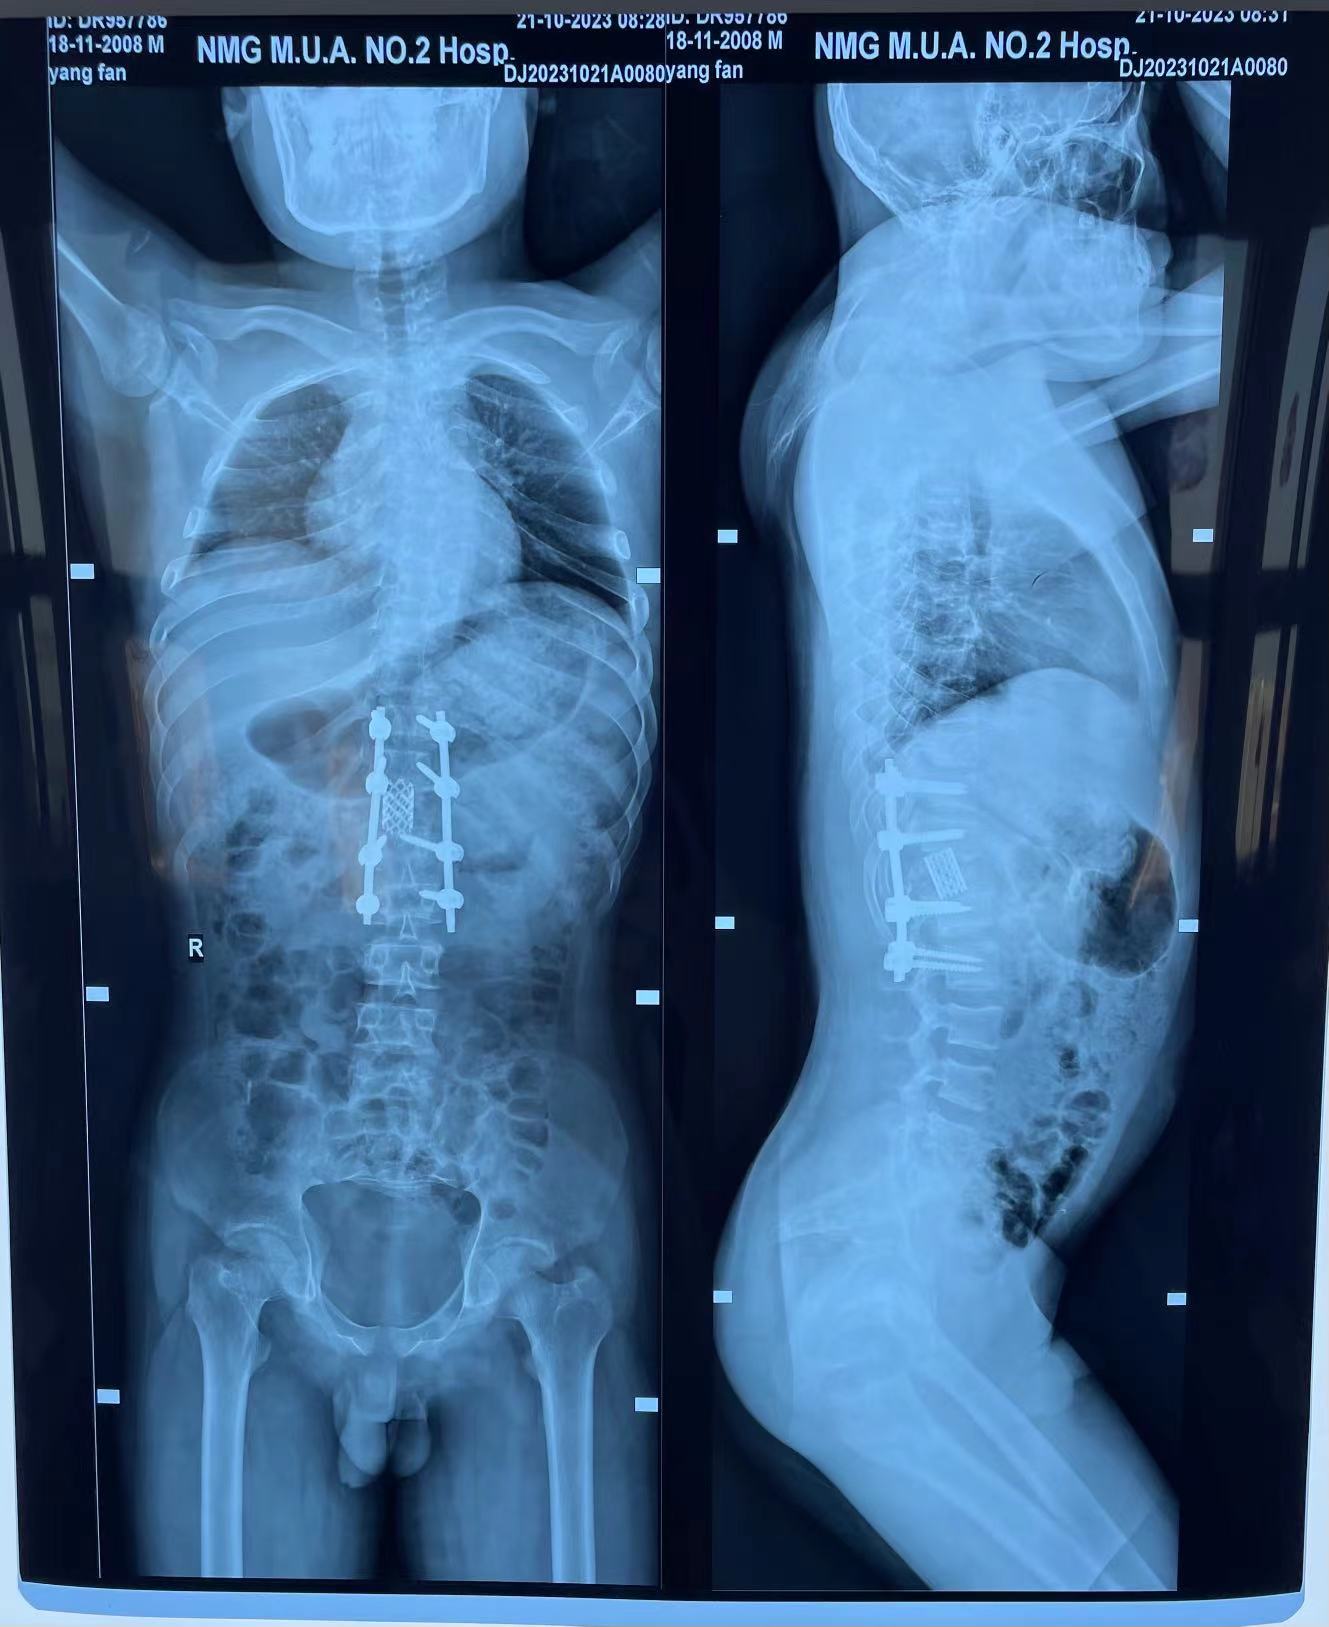

脊柱外科中心D区辛大奇、王东海、孙洪岩医疗团队完善患者术前检查后,明确诊断为胸12半椎体侧后凸畸形,经过积极与胡侦明教授沟通、讨论后,共同为患者制定手术方案,为患者施行先天性脊柱侧弯、半椎体侧后凸畸形截骨矫形+植骨融合内固定术。

胡侦明教授不远万里,亲临我院参加会诊并给予手术指导,最终在胡教授和我院医护团队的通力协作下,手术顺利完成,患者术后继续接受恢复治疗,状态良好,患者双下肢功能明显改善。近日,患者已顺利康复出院。